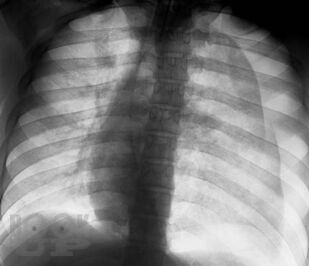

В книге изложены особенности клинической и рентгенологической диагностики повреждений и ранних осложнений закрытых травм грудной клетки. Проведен анализ объективных причин, затрудняющих основные и дополнительные методы исследования. На 240 рентгенограммах показаны признаки трудновыявляемых повреждений и осложнений травм грудной клетки, в частности пневмоторакса, гемоторакса, ателектаза, разрыва диафрагмы. Впервые отмечается клиническая значимость напряжения в малом пневмотораксе при политравме. Приведены сравнительная характеристика и алгоритм дифференциальной диагностики острых диффузных поражений легких при травме. Описан опыт выявления и решения проблемы нефункционирующего дренажа плевральной полости. Издание предназначено для хирургов, торакальных хирургов, травматологов, реаниматологов, оказывающих помощь больным с политравмой.